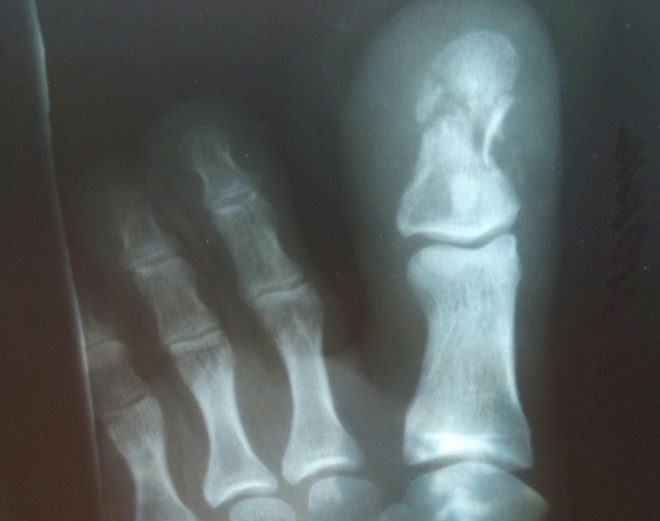

При любом виде перелома до сих пор золотым стандартом считается рентгенологическое исследование. Этот безболезненный способ диагностики не требует специальной подготовки и с высокой достоверностью позволяет подтвердить или опровергнуть наличие перелома. С его помощью устанавливаются характер травмы и степень смещения костных отломков.

В сложных диагностических случаях может быть назначено проведение компьютерной или магнитно-резонансной томографии. Исследования с большой точностью позволяют выявить разной степени переломы с наличием внутрисуставных травм или повреждением окружающих мягких тканей. От того, насколько точно будет установлен диагноз, напрямую зависит эффективность лечения.